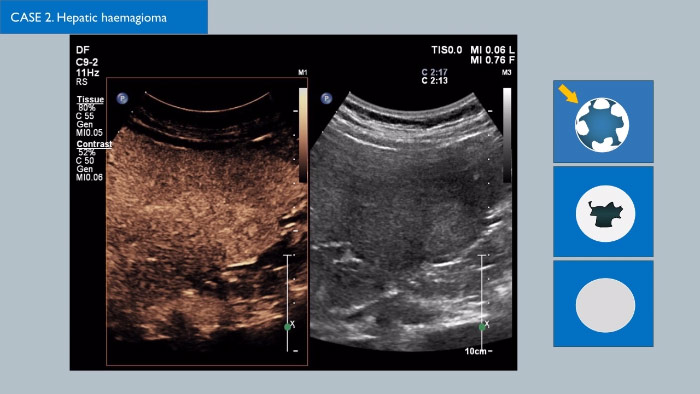

Los agentes de contraste para ultrasonidos pueden transformar el papel que desempeñan los ultrasonidos, pues permiten que los profesionales sanitarios estudien los patrones de mejora de las lesiones hepáticas en tiempo real, lo que ofrece la posibilidad de realizar diagnósticos más definitivos y rápidos.

Con los ultrasonidos de Philips, los ultrasonidos con contraste se integran a la perfección en el flujo de trabajo normal y proporcionan un nivel de detalle excepcional en exploraciones de la fase arterial, portal y tardía.  Además, gracias a tecnologías avanzadas como MaxVue, el transductor PureWave C9-2, las imágenes de fusión, la cuantificación integrada mediante las Q-App de Philips y la solución hepática definitiva, ya es posible sentir una seguridad total incluso en las exploraciones más complicadas. Soluciones innovadoras como la tecnología xMATRIX 3D/4D también pueden dar un giro a la evaluación de las lesiones hepáticas, pues proporcionan un método rápido y eficaz de visualizar los vasos nutricios y la respuesta al tratamiento.  Existen multitud de avances fascinantes en el campo de los CEUS; haga clic en el enlace para ponerse en contacto con su representante local de Philips.